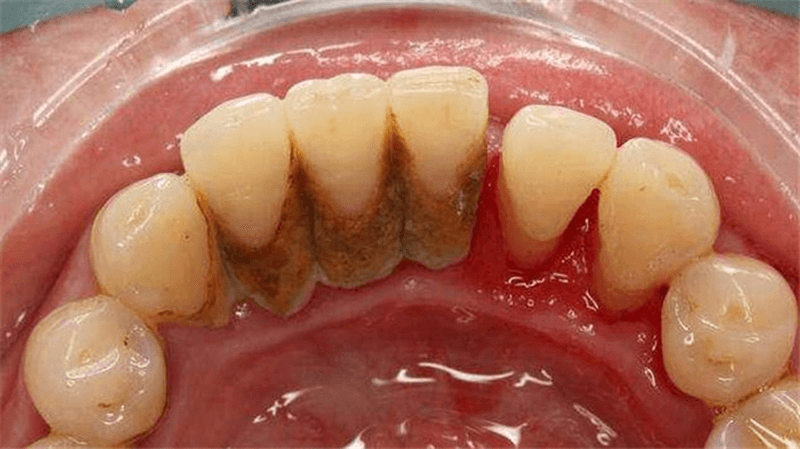

Hình ảnh cao răng

Cao răng hay còn được biết đến là vôi răng, bản chất là các muối canxi kết hợp với phosphate, hình thành từ các vụn thức ăn, muối trong nước bọt và các chất khoáng ở trong miệng. Khi sử dụng một chiếc gương và há miệng soi, bạn sẽ dễ dàng quan sát thấy tại vị trí các chân răng có bám một lớp màu vàng ố hoặc thậm chí nâu đen rất chắc chắn và đó chính là cao răng đã được hình thành.

Chính bởi tính cứng của cao răng mà rất nhiều người nhầm tưởng đó là men răng mới được hình thành và vô tư để lớp cao răng này phát triển dày lên. Trên thực tế thì ngược lại, cao răng cứng song có cấu trúc rỗng, xốp, là nơi lý tưởng cho hàng ngàn vi khuẩn trú ngụ và phát triển. Khi cao răng được hình thành, các mảng bám thức ăn có xu hướng tích tụ tại những vị trí này nhiều hơn khiến cao răng dày hơn, dần dần ăn sâu xuống chân răng. Từ đây cũng là căn nguyên gây nên một loạt các vấn đề về răng miệng như viêm nha chu, tụt lợi, viêm mòn chân răng, sâu răng,…. Chính bởi vậy mà các bác sĩ nha khoa luôn khuyên bạn nên loại bỏ cao răng và giữ răng không có những mảng bám vôi răng này.

Thăm khám ban đầu là bước bắt buộc cho tất cả các thăm khám và điều trị răng miệng từ đơn giản đến phức tạp. Khi đi lấy cao răng, bác sĩ cũng sẽ thăm khám để xác định mức độ vôi răng của bạn ở mức nào. Thông thường có 3 mức độ vôi răng, mức 1 là nhẹ nhất, không có quá nhiều mảng bám. Mức 2 là mức mảng bám xuất hiện khá nhiều và che lấp toàn bộ chân răng. Mức 3 trở lên là tình trạng vôi răng rất nặng, đã bắt đầu gay tụt lợi, viêm lợi hay viêm nha chu,…. Song song với xác định mức độ vôi răng, bác sĩ cũng sẽ phát hiện các bệnh lý răng miệng nếu có của bạn.